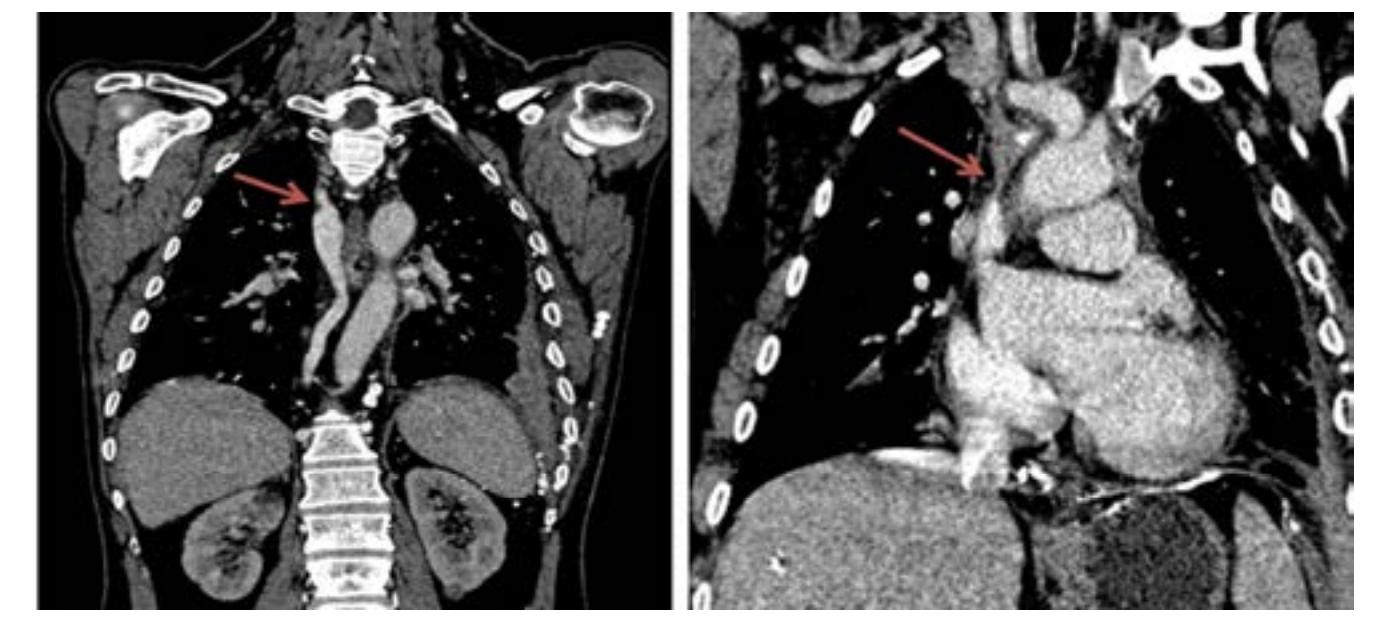

The caval stenosis, in the series, was diagnosed by means of an angio CT scan of the chest, followed by confirmation using the venacavogram.

In what concerns the place of imaging exploration, the majority of authors believe that CT-scan with its high-quality multiplanar reconstructions is a crucial imaging tool. In fact, angio-CT scan confirms the diagnosis, determines the exact extent of obstruction, the nature and the degree of vena cava obstruction as well as it orients the placement of the endoprosthesis and the presence of associated pathologies.6 A venographic classification according to Stanford and Doty was set. Four Patterns of venous collateral return have been described.5 The 4th one matches with the most severe in terms of clinical symptoms (Schema 1).